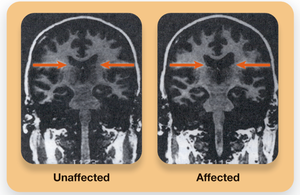

Brain Differences: Enlarged ventricles, reduced frontal cortex activity, increased dopamine (DA) activity (positive symptoms), and underactive glutamate (GLU) systems (negative symptoms).